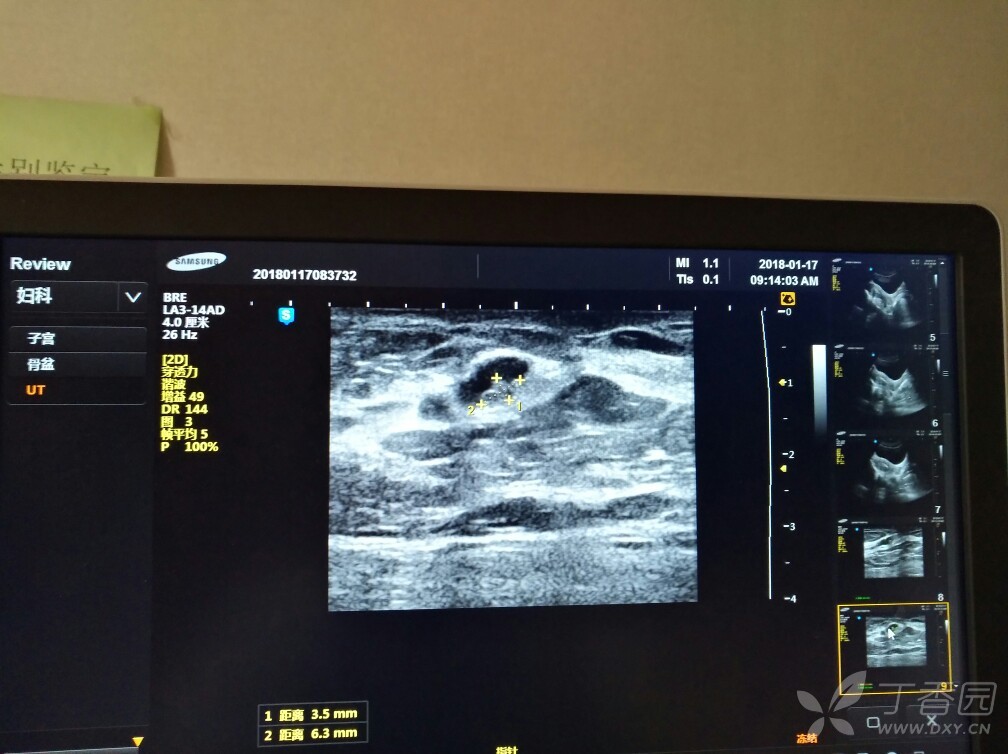

妻子的乳腺彩超,各位外科同仁给看下怎么治疗合适

图片尺寸1042x1030